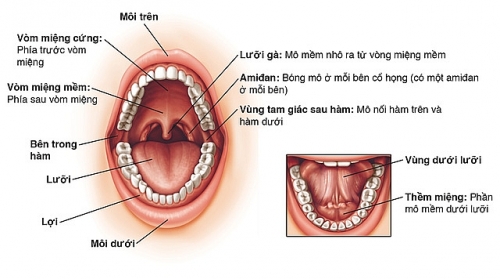

Dấu hiệu nhận biết ung thư khoang miệng

Bài viết này sẽ cung cấp cho bạn những thông tin cần thiết về bệnh ung thư khoang miệng: Dấu hiệu nhận biết ung thư khoang miệng là gì? Cách phòng tránh bệnh như thế nào?